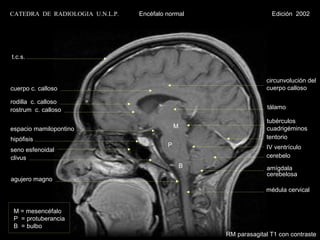

t.c.s.

circunvolución del

cuerpo c. calloso                                                  cuerpo calloso

rodilla c. calloso

rostrum c. calloso                                                  tálamo

tubérculos

espacio mamilopontino                         M                    cuadrigéminos

hipófisis                                                          tentorio

P                        IV ventrículo

seno esfenoidal

clivus                                                             cerebelo

B                amígdala

cerebelosa

agujero magno

médula cervical

M = mesencéfalo

P = protuberancia

B = bulbo

RM parasagital T1 con contraste